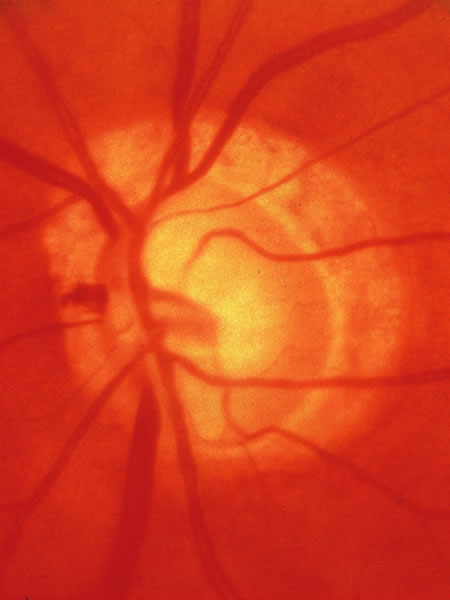

Usually all other forms of optic nerve disease (and inner retinal disease) produce simple atropy of the disc without cupping (Figs. 34 to 36), but occasional cases of cupping have been seen with anterior ischemic optic neuropathy, particularly due to giant cell arteritis (Figs. 37 and 38).

Fig. 37. Swollen optic nerve superiorly during anterior ischemic optic neuropathy caused by giant cell arteritis.

Fig. 38. Same eye after resolution of the attack, with excavation extending to the superior rim of the disc, mimicking the appearance of glaucomatous cupping.